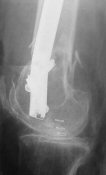

THX, initial images are

1,

2.

KEMMD> - Your last posted case: how is possible to have secure fixation with

KEMMD> applied construct without additional casting, bracing or Ilizarov?

At that moment we had in stock only the 10 mm solid nails so of course there was no idea about early weight bearing. But it was quite enough for early knee ROM excersises (see attached). Two locking screws through the distal block provided that.